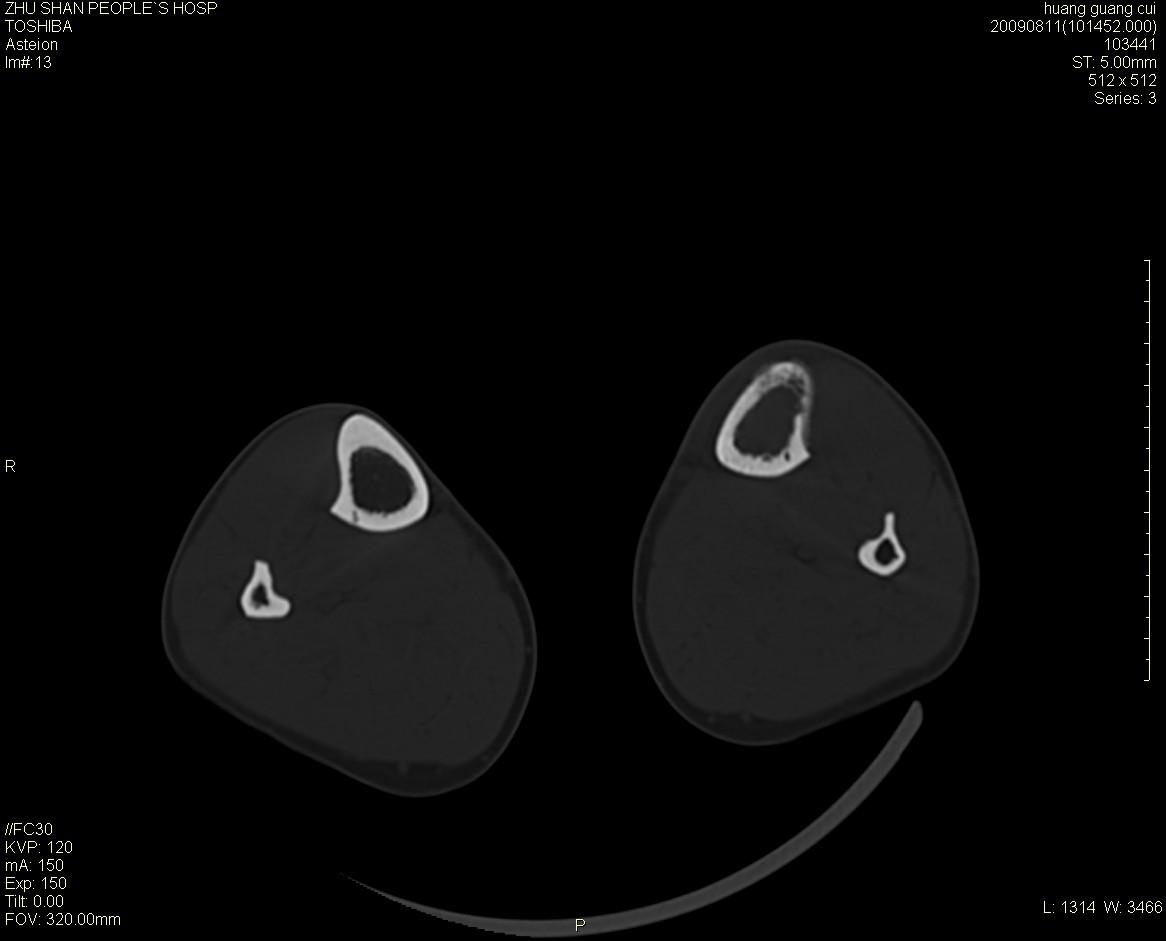

左侧胫骨中段骨皮质溶骨性破坏,髓腔内外见软组织肿块,无明显钙化及成骨,定位相显示病变周围“筛孔样”改变,定性恶性无疑,原发或转移均有可能,倾向于骨纤维肉瘤可能性大,转移瘤不排除。膝关节以下骨转移很少,且要有原发灶支持,尤文氏肉瘤年龄太大不支持。